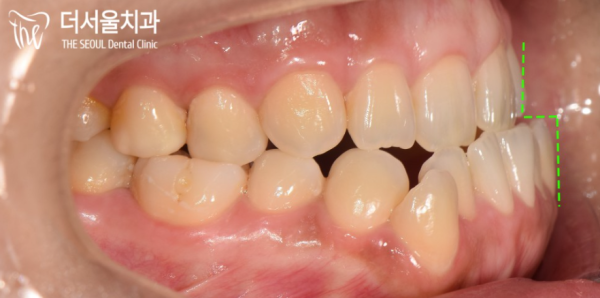

이 환자분은 입을 다물고 있어도 아래턱이 나와있었습니다.

육안으로 확인해 보면, 위턱에 비해 아래턱이 발달한 케이스로

Class 3급 부정교합(주걱턱)으로 확인이 됩니다.

This patient's jaw was sticking out even if he kept his mouth shut.

If you look at it with your eyes, the lower jaw is more developed than the upper jaw

Class 3 malocclusion (paddle jaw) is confirmed.